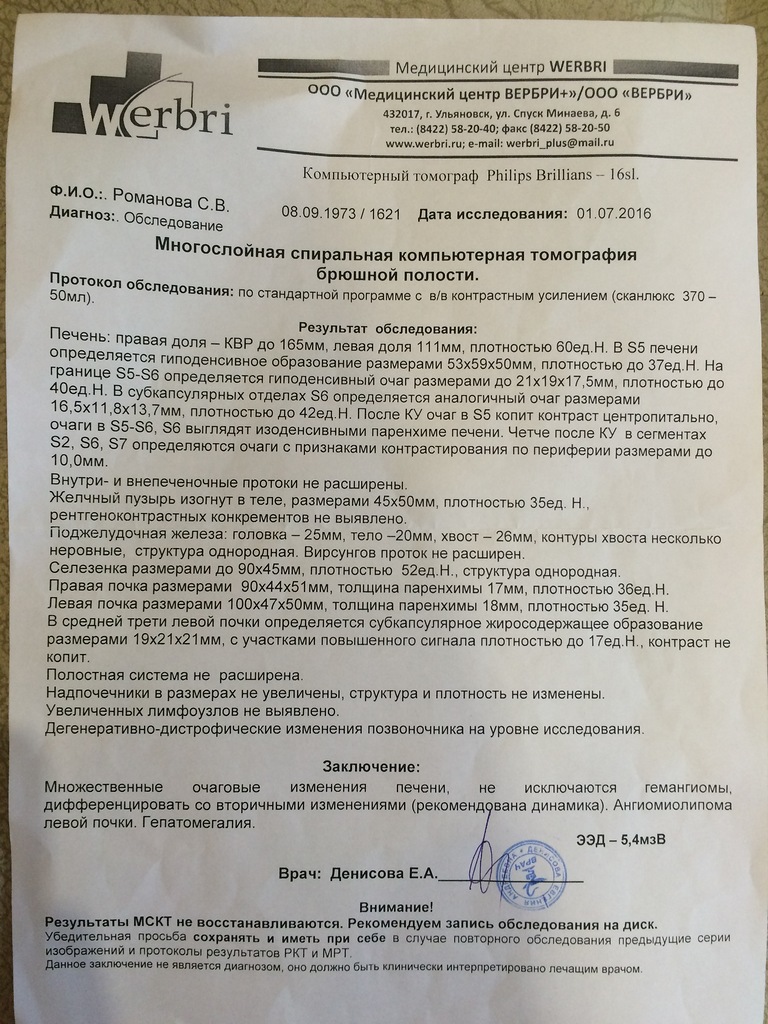

Методы динамического контрастирования печени на МРТ

Раздел: Снимки-подсказки